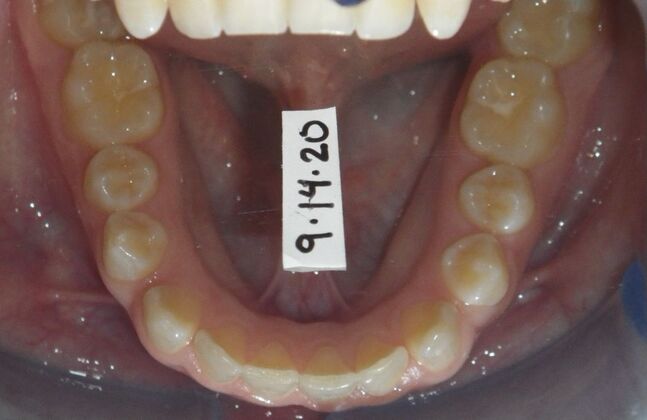

Patient presents desiring all spaces on upper and lower teeth closed. She will need slight expansion of upper arch due to lower molars leaning inward toward tongue. Used nitanium palatal expander with built in rotation of upper molars and lower lip bumper to upright lower first molars. Patient was also informed that her upper lateral incisors would require bonding due to their small size to close all space.